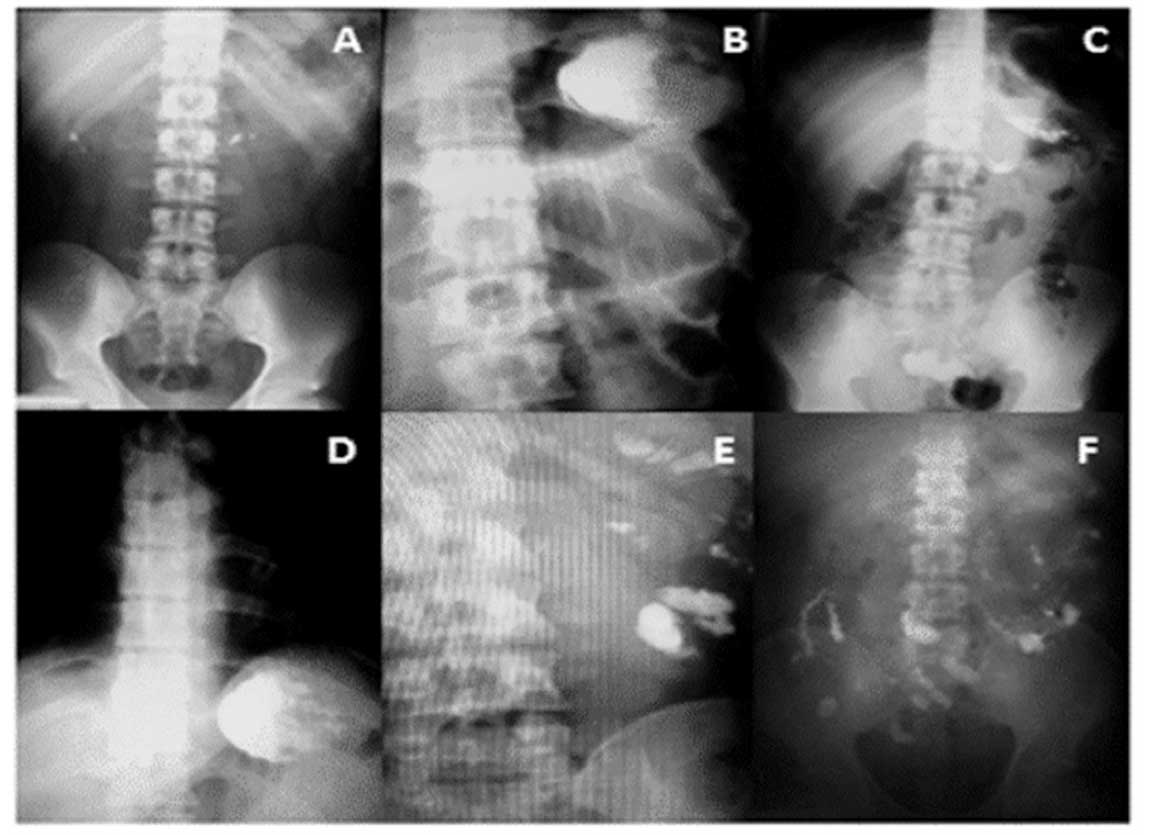

En la figura 1 se aprecian las imágenes radioópacas características de estas intoxicaciones.

En la valoración radiográfica de nuestros pacientes se encontraron indicios de la presencia de fosfuro metálico en zonas medias y bajas de la radiografía simple de abdomen. En la literatura se ha mencionado la presencia de estas radioopacidades en las intoxicaciones por otros metales, pero existen escasos reportes de la presencia de estos datos radiográficos en la intoxicación por fosfuros metálicos y no se había analizado previamente como un factor interviniente en la mortalidad; sin embargo, dada la naturaleza química de los fosfuros metálicos es esperado que puedan encontrarse estos hallazgos radiográficos.13,14,15,16 La presencia de tóxicos en la radiografía abdominal se puede asociar a la falta de descontaminación en forma adecuada y, aun cuando fue un factor analizado en nuestro estudio, solamente se evaluó el tiempo de realización y no la técnica utilizada, por lo que fue una debilidad de nuestro proyecto que pudo influir en que este sea un factor interviniente en la mortalidad de forma aislada.17,18

Las fortalezas de este trabajo son las implicaciones clínicas identificadas, ya que dejan clara la importancia de actuar rápida y enérgicamente en la descontaminación de alta calidad del paciente (aislamiento de vía aérea, lavado gástrico temprano y lavado intestinal total con soluciones/catárticos), teniendo como marcador de calidad y monitorización la placa de abdomen (factor de riesgo de gran magnitud y vulnerabilidad), en la que al aparecer las huellas del tóxico dejan en evidencia la necesidad de continuar con la descontaminación de alta calidad.

La intoxicación por fosfuros metálicos tiene una alta mortalidad y está fuertemente asociada a la evidencia radiográfica del tóxico, misma que sirve para diagnosticar, pronosticar y monitorizar la adecuada descontaminación.

La evidencia radiográfica en la región media e inferior y el tiempo de la primera atención médica son los principales factores asociados a la mortalidad y conllevan una alta vulnerabilidad.